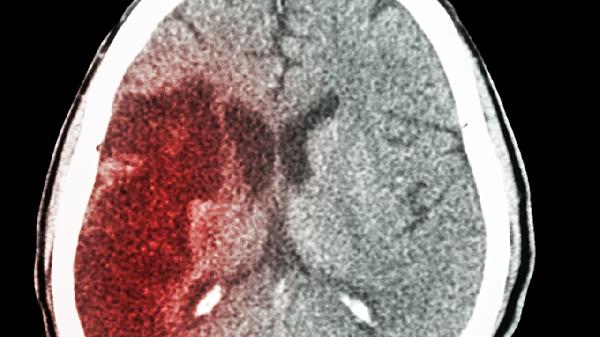

早上起床手指一阵刺痛,像被无数小蚂蚁啃咬?地铁上突然脚底板发麻,像踩在棉花堆里?别以为这只是压到神经的小事,身体正在用特殊方式拉响警报。这种来去匆匆的麻木感,可能是血管发出的求救信号。